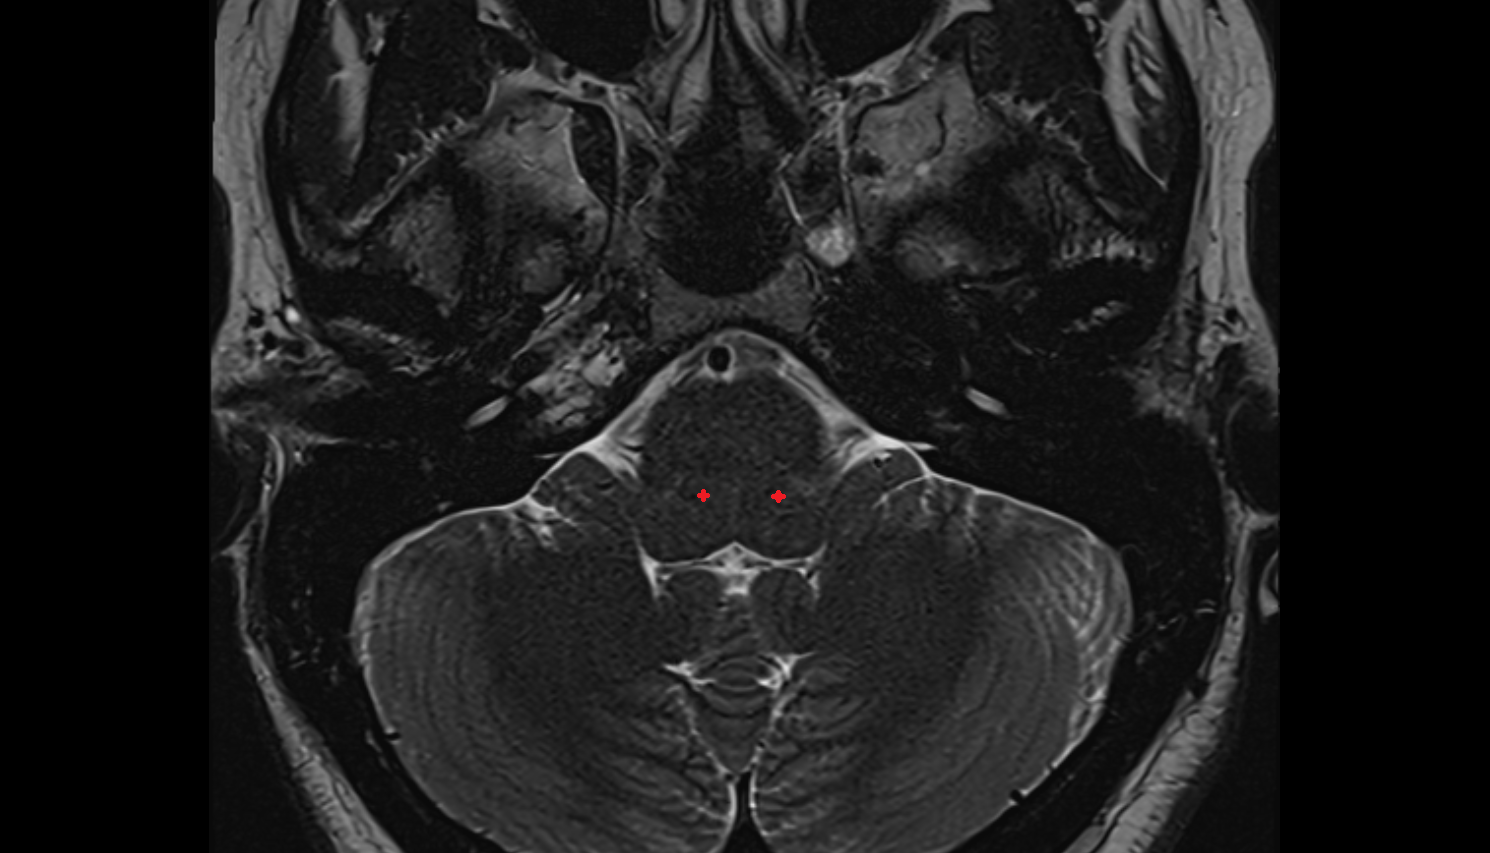

- Middle cerebellar peduncle

- Dorsal root of spinal nerve

- Cisterna magna